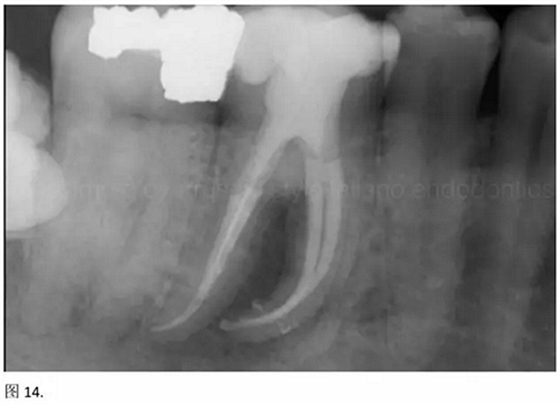

結(jié)論:本文的目的是描述一種旨在優(yōu)化根管根尖部分預(yù)備的預(yù)敞技術(shù)。根管頸部或冠方的早期預(yù)敞對于減少初尖銼直徑和根尖部根管直徑之間的差異至關(guān)重要。大量研究表明,手用或機(jī)用器械預(yù)敞根管能顯著減少器械折斷的發(fā)生率。下一篇文章將描述如何建立可重復(fù)的引導(dǎo)路徑。而引導(dǎo)路徑是指鎳鈦器械可沿著光滑根管壁輕易地滑行至工作長度的通路。